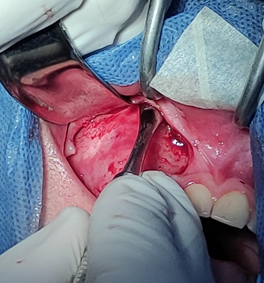

Luego de esperar el periodo de latencia del anestésico (3min), se colocó el campo abierto sobre el área de trabajo para proceder con la siguiente fase, una vez confirmada la anestesia en la zona se procede a la incisión con hoja de bisturí n°15 colocada en un mango n°3, se realizó un colgajo sulcular desde la UD 17 hasta la cara mesial de la UD 13 donde se realizó la descarga en dirección al fondo del surco, luego se realizó levantamiento del colgajo de espesor total con el periostótomo Molt #9. Esto se muestra en la figura 7.

Figura 7. Levantamiento de colgajo mucoperióstico con Molt #9 usando separadores de Branemarck y Minnesota.

Fuente: Historia Clínica Postgrado Cirugía bucal ULAC-IDOLA Julio 2021